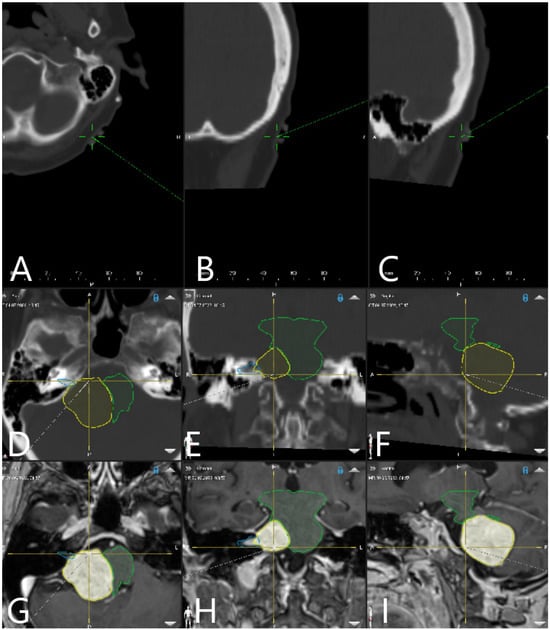

| Patient Number | Segmented Structures in AR Advantages: Craniotomy Planning, Dural Opening, Relations of Tumor to CN V, Localization of Origin of CVI and CVIII at the Brain Stem, Relations of Tumor to Brain Stem, Localization of IV Ventricle, Segmentation of Tumor Cyst, Localization of Structures of the Middle Ear for Facilitation of Drilling on Inner Acoustic Meatus, Relations of Tumor to Arterial Vessels and to Petrosal Vein | ||||||||||

|---|---|---|---|---|---|---|---|---|---|---|---|

| Sigmoid Sinus | Transverse Sinus | Tumor Outline | CN VII and VII Origin at Brain Stem | CN V | Petrous Vein | Arterial Vessels (AICA, PICA, SCA) | Brain Stem | Middle Ear, Cochlea and Semicircular Canals | Pyramidal Tract | IV Ventricle | |

| 28 | + | + | + | − | − | − | + | − | − | − | − |

| 29 | + | + | + | − | − | + | + | − | − | − | − |

| 30 | + | + | + | − | − | + | + | + | − | + | − |

| 31 | + | + | + | − | − | + | − | + | + | − | − |

| 32 | + | + | + | − | − | − | − | + | + | − | + |

| 33 | + | + | + | + | − | − | − | + | − | − | + |

| 34 | + | + | + | + | − | − | − | + | + | − | − |

| 35 | + | + | + | + | − | − | − | + | + | . | − |

| 36 | + | + | + | + | + | − | − | + | − | − | − |

| 37 | + | + | + | − | − | + | − | + | + | − | − |

| 38 | + | + | + | + | + | + | − | + | + | − | − |

| 39 | + | + | + | − | + | − | − | + | + | − | − |

| 40 | + | + | + | + | + | − | − | + | + | − | − |

| 41 | + | + | + | − | + | − | − | + | + | − | − |

| 42 | + | + | + | + | + | − | − | − | − | − | |

| 43 | + | + | + | + | + | + | − | + | + | − | − |